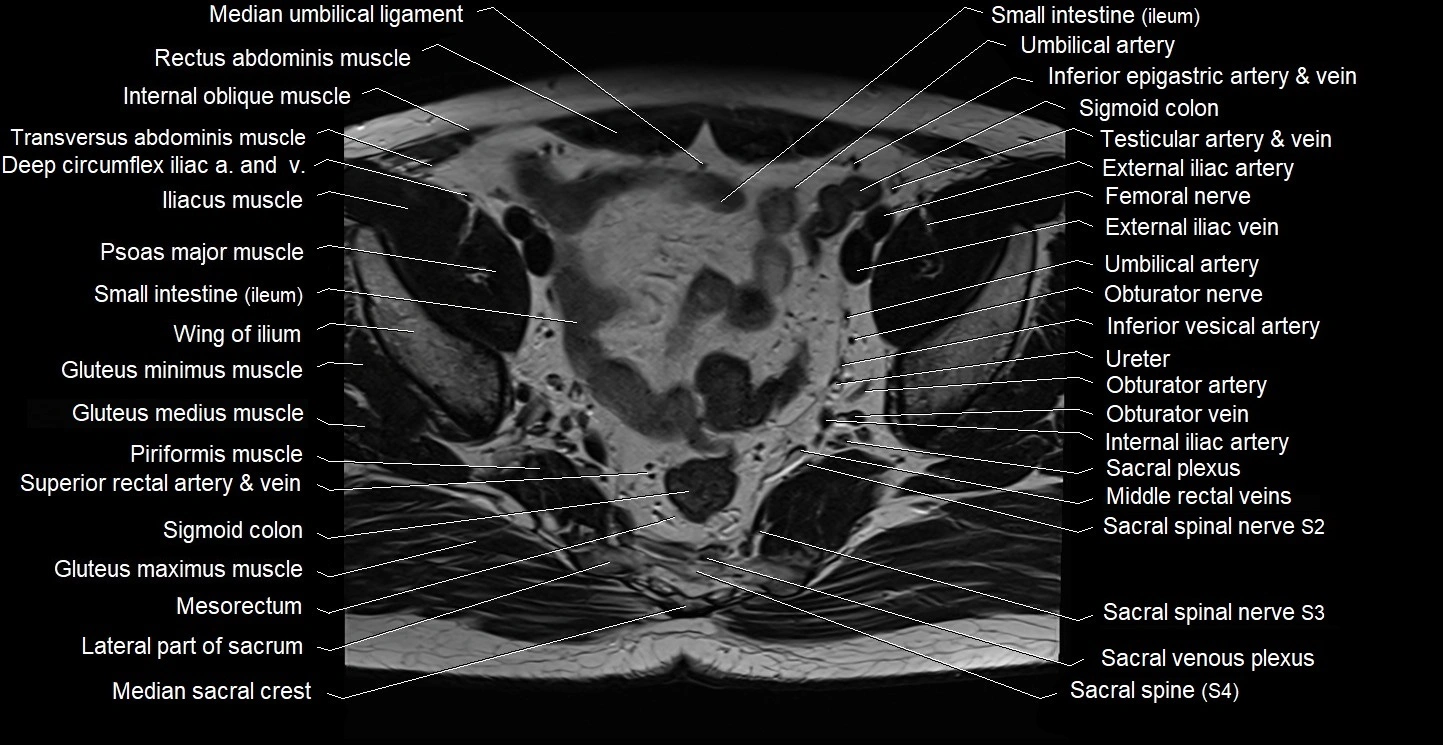

- Ala of ilium (wing of ilium)

- Ala of sacrum

- Body of ilium

- Body of urinary bladder

- Common iliac lymph nodes

- Common iliac vein

- External iliac artery

- External iliac lymph nodes

- External iliac vein

- Femoral nerve

- Genitofemoral nerve

- Gluteus maximus muscle

- Gluteus medius muscle

- Gluteus minimus muscle

- Inferior mesenteric artery (IMA)

- Inferior mesenteric vein

- Inferior vesical artery

- Internal iliac artery

- Internal iliac vein

- Internal oblique muscle

- Lateral part of sacrum

- Left ureter

- Lumbosacral trunk

- Median sacral crest

- Median sacral vein

- Median umbilical ligament

- Mesorectum

- Piriformis muscle

- Psoas major muscle

- Pubic bone

- S (Sacral spine)

- Sacral canal

- Sacral cornu (sacral horn)

- Sacral hiatus

- Sacral plexus

- Sacrospinous ligament

- Sigmoid colon

- Small intestine

- Superior rectal artery

- Superior rectal vein

- Transversus abdominis muscle

- Umbilical artery

- Ureters